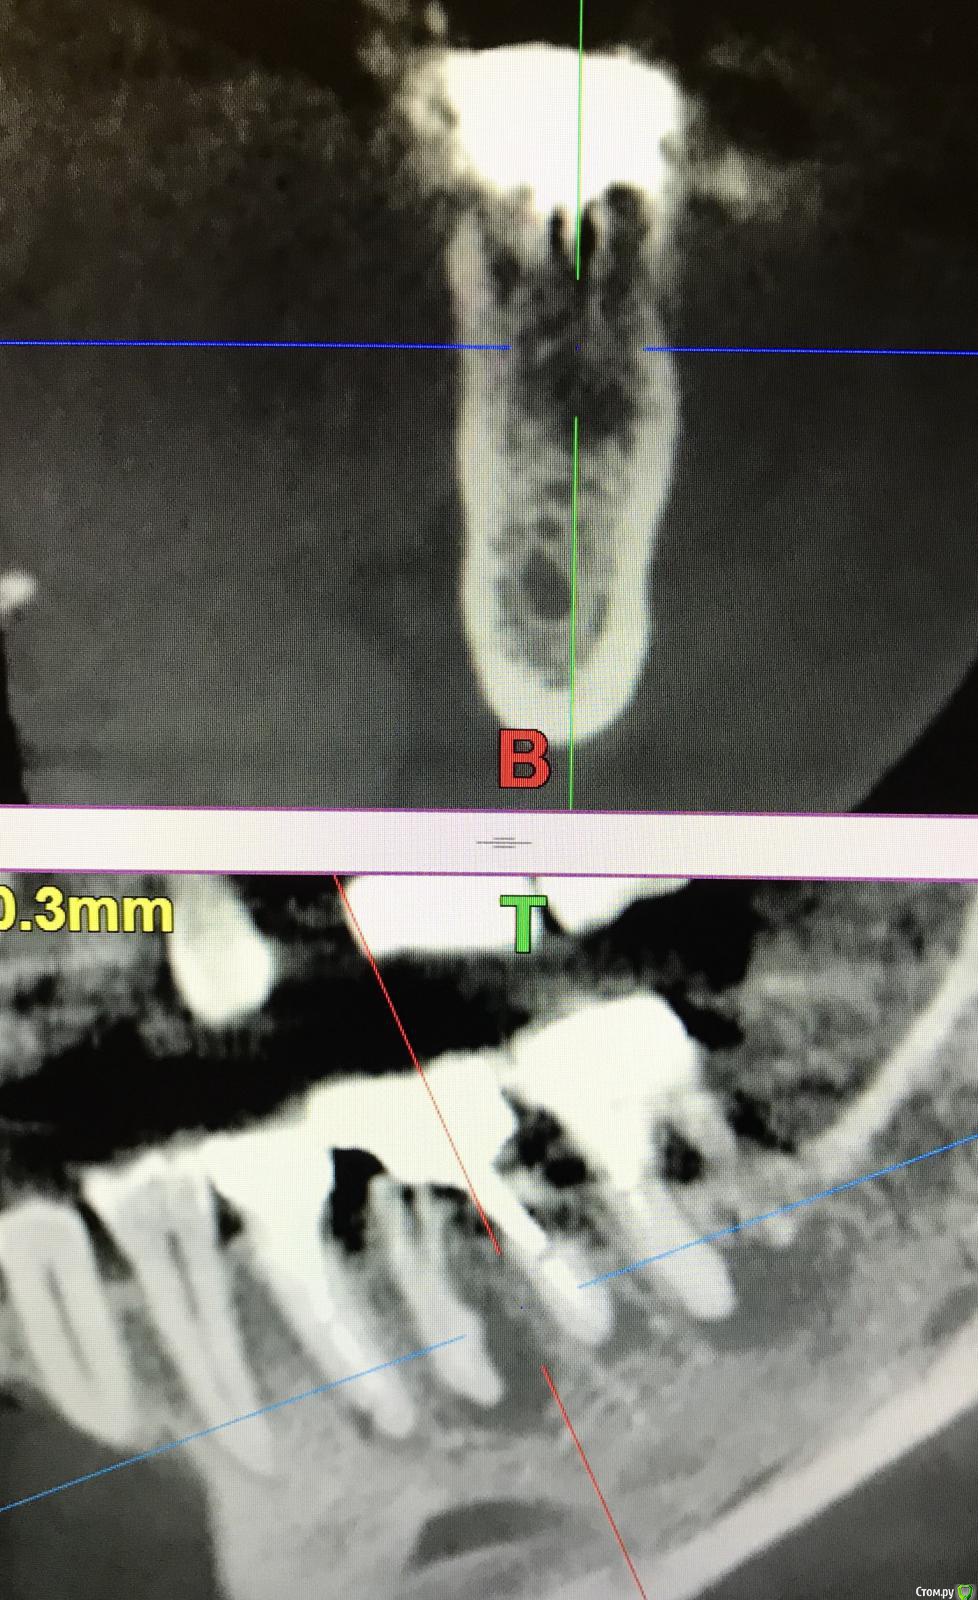

annda Опубликовано 7 августа, 2018 Поделиться Опубликовано 7 августа, 2018 (изменено) Тоже попробовала.Застарелый перелом корня.Два свища на момент приема.Удаление всего,спилила на коронковом фрагменте до связки,канал закрыла IRMом,в дефект порошок Лилпласт на АPRF ,обратно фрагмент притопила,фиксация на ретейнер.Снимок через две недели.Теперь думаю,не длинноват ли фрагмент.Хотя,может и проекция снимка вводит в заблуждение.КТ срезы сняла с экрана,пардон за качество. Изменено 7 августа, 2018 пользователем annda 3 Ссылка на комментарий

Bier Опубликовано 7 августа, 2018 Автор Поделиться Опубликовано 7 августа, 2018 ну вроде как длинный фрагмент даже лучше. Советую через 2-3 мес вытянуть его ортодонтически и только потом удалить. Ссылка на комментарий

annda Опубликовано 8 августа, 2018 Поделиться Опубликовано 8 августа, 2018 (изменено) Ортодонтически—может просто ретейнер переклеить?Он не обожжен... Изменено 8 августа, 2018 пользователем annda Ссылка на комментарий